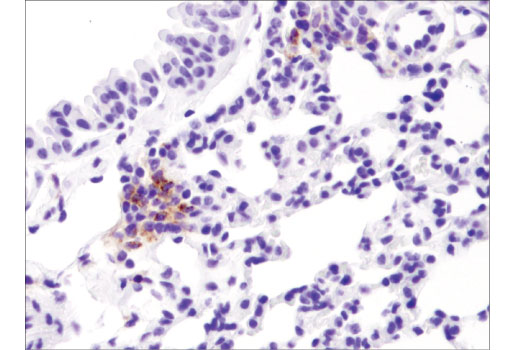

Immunohistochemical analysis of paraffin-embedded normal mouse lung using PD-L1 (D5V3B) Rabbit mAb.

Immunohistochemistry Image 2: PD-L1 (D5V3B) Rabbit Monoclonal Antibody